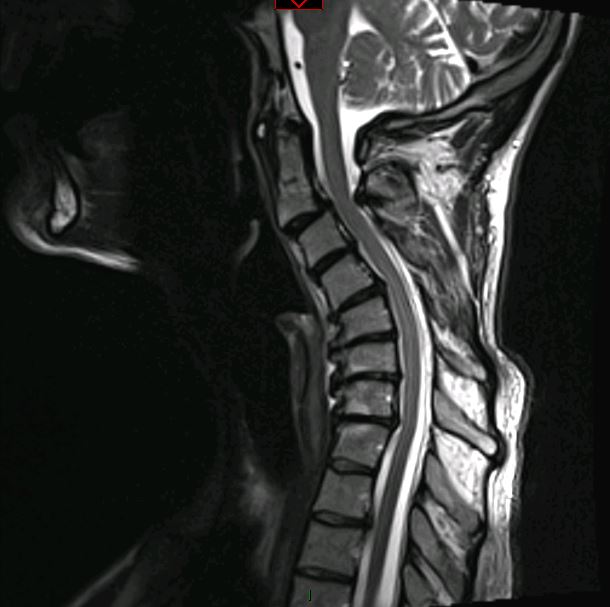

Imaging Gallery

Before & After

Spine Surgery

All imaging is fully de-identified. Patient identifiers removed in compliance with HIPAA.